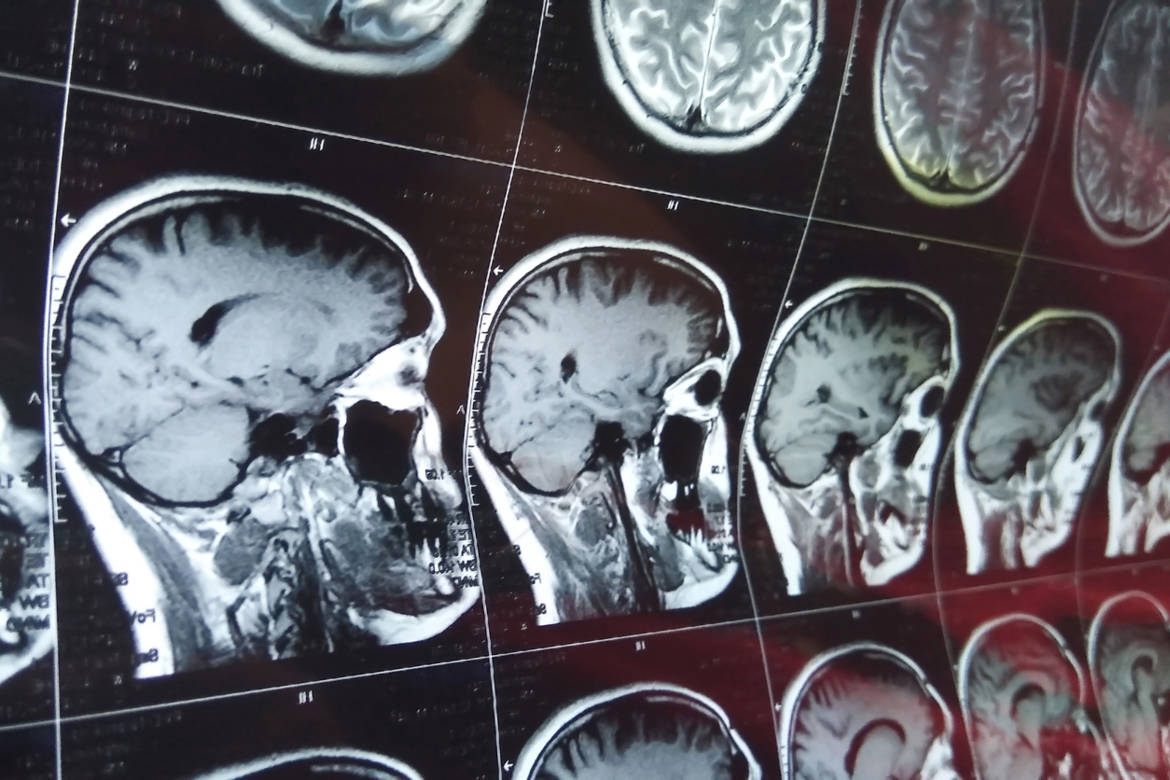

Trouver les principes de base du fonctionnement du cerveau, cʹest lʹambition des neurosciences computationnelles.

Cʹest tout ce pan de recherches en neurosciences qu'Huma Khamis vous propose de découvrir aujourdʹhui.

Avec Alexandre Pouget, professeur au Département des neurosciences fondamentales de lʹUniversité de Genève, et Romain Brette, chef dʹéquipe des neurosciences computationnelles à lʹInstitut de la vision à Paris.